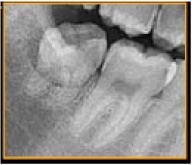

当診療所では、歯科用3Dパノラマ撮影装置(エクセラスマート F+)を導入しております。

これまで以上に、より正確に患部の状態を把握できるようになり、患者様に精度の高い、安全で確実な歯科診療を提供することができるようになりました。

①高画質

従来に比べ、より高画質で高精度の画像撮影が可能に。

歯根の形態から上顎洞・顎関節等に至るまで、総合的により細部の把握が可能になり、1枚の写真で的確な診断が容易にできるようになりました。

小型:最小80μmの

ボクセルサイズを実現

歯根の形態や根尖方向などの

細部の撮影~把握が可能です。